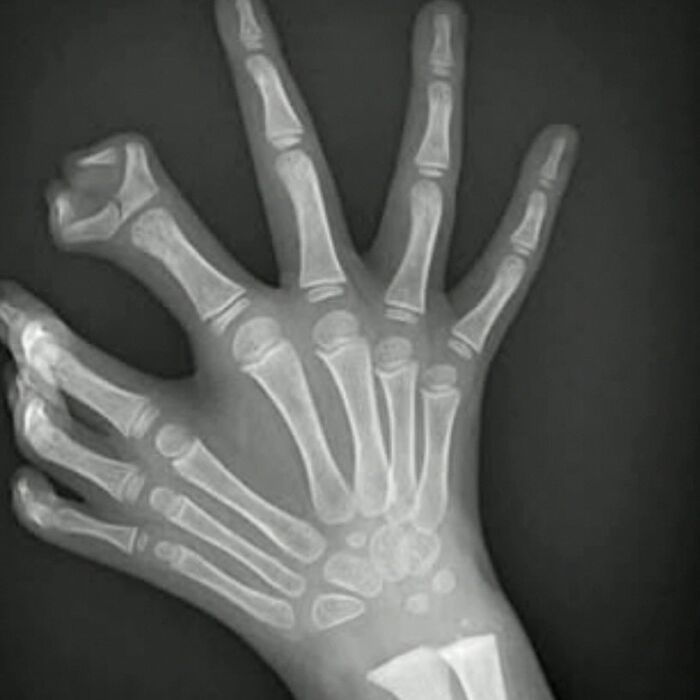

Is there something strange about this picture? You’re right, the hand shouldn’t normally bend this way!

Often referred to as „double jointed“ people who can move their joints beyond its normal range have what are called hypermobility. What the gentleman’s have in this picture is called Ehlers-Danlos Syndrome, the hyper-mobility form, an inherited connective tissue disorder that is caused by defects in a protein called collagen. Symptoms include varying degrees of hyperextensive skin, joint hypermobility, and tissue fragility (including that of vasculature - leading to risk of aortic dilation, aneurysms, or dissection in the severe form).

Most babies and children are naturally very flexible. Many people become less flexible as they grow, but hypermobility continues into adulthood for some, up to about 20% of people. Being „flexible,“ „bendy,“ or „double-jointed“ is not usually a problem, and for some, like dancers or gymnasts, it is an advantage. Hypermobility that does not cause pain or other symptoms is referred to as „asymptomatic joint hypermobility“ and does not need to be treated. The problem occurs when joints are not just hypermobile but are also unstable. Joint instability occurs when the bones of a joint aren’t held in place securely. This can lead to joint subluxations, dislocations, sprains, and other injuries. Joint instability can cause both acute and chronic pain and interfere with daily life.